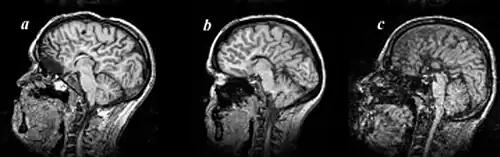

Agenesis of the corpus callosum (ACC) is a rare birth defect in which there is a complete or partial absence of the corpus callosum. It occurs when the development of the corpus callosum, the band of white matter connecting the two hemispheres in the brain, in the embryo is disrupted. The result of this is that the fibers that would otherwise form the corpus callosum are instead longitudinally oriented along the ipsilateral ventricular wall and form structures called Probst bundles.

Callosal disorders can be diagnosed through brain imaging studies or during autopsy.[8] They may be diagnosed through an MRI, CT scan, Sonography, prenatal ultrasound, or prenatal MRI.[1]